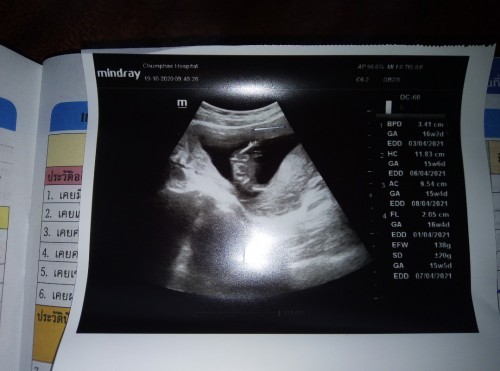

ไปหาหมอมาหมอบอกแค่ว่าเด็กปกติดีแต่ไม่ได้บอกว่าเป็นผญหรือผชแม่ๆช่วยดูหน่อยค่ะท้องได้16วีคค่ะ #ท้องแรกคะ

16 week หมออาจจะยังเห็นไม่ชัดเลยไม่ได้บอกค่า